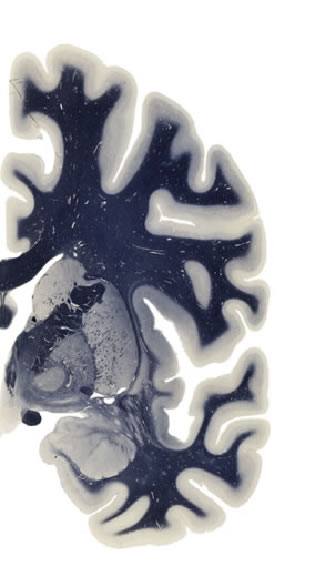

Hi-Resolution Sections · Cells (Nissl Staining) · Virtual Microscopy

Frontal sections (Nissl) from the Atlas Brain:

Slice ID:

r3-1225

Plate NR:

ca 25-26

Position:

4,7 mm